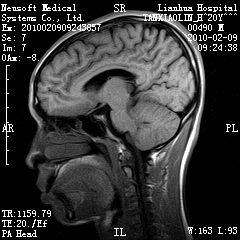

20岁男性患者,平时偶有头痛而无其他不适,现因持续头痛服药后无缓解而来院就诊。

松果体区占位继发轻度脑积水?该患者有ct资料,我已发上。

考虑松果体囊肿。